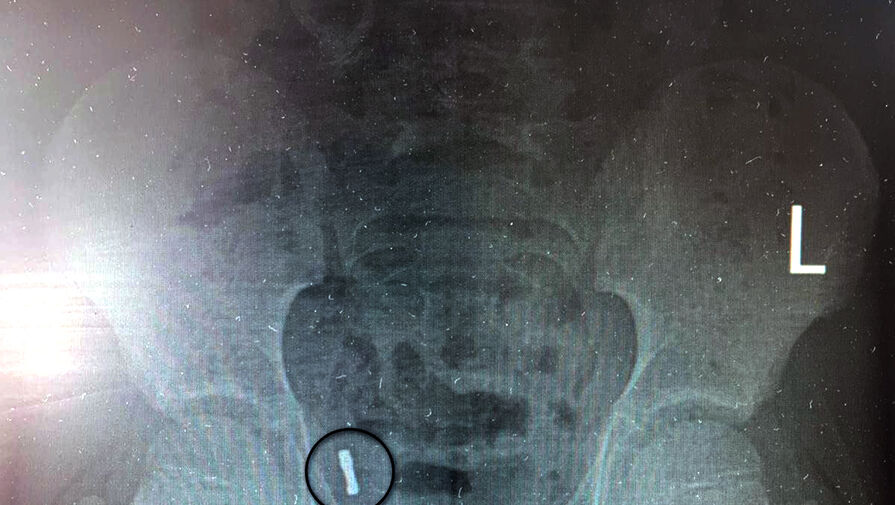

К моменту обращения за помощью инородные предметы мигрировали в аппендикс, что выявил рентген. Медики отметили, что инородные тела крайне редко попадают в аппендикс. За ребенком наблюдали трое суток, после чего приняли решение о проведении операции из-за риска перфорации и развития перитонита.

«Под общим обезболиванием медики провели ревизию брюшной полости, таким образом подтвердив нахождение магнитов в аппендиксе. Специалисты провели типичную аппендэктомию – удалили аппендикс», — рассказали в пресс-службе.